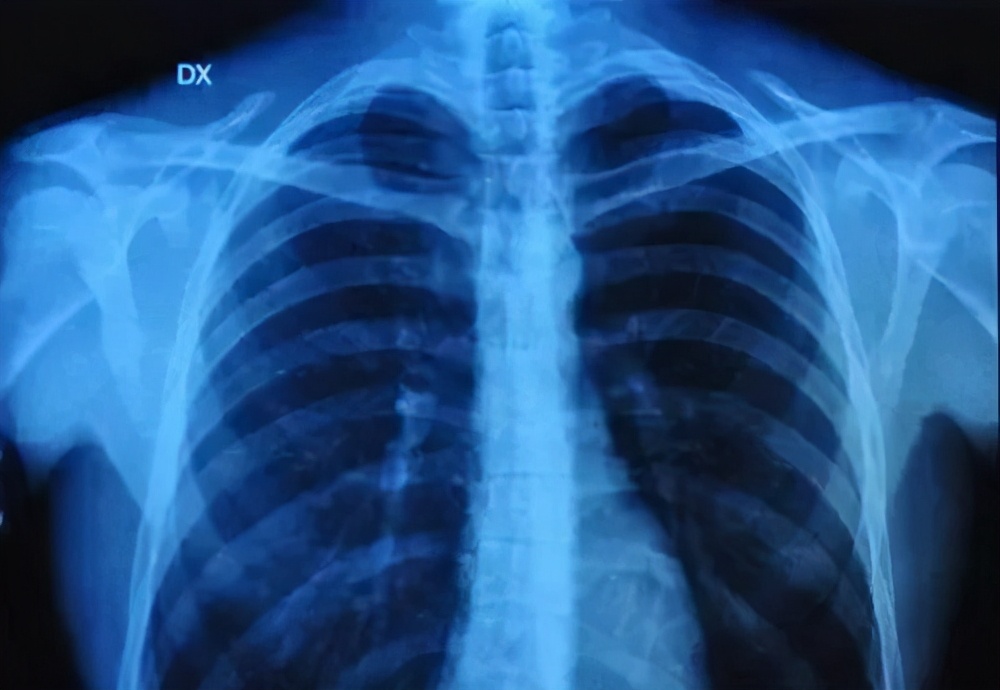

用X光片查肺癌

发烧、咳嗽,怀疑肺部感染炎症时,X光片是一种简单、实用的检查方式。

但如果体检中心,以此来筛查肺癌实在时没什么必要。

因为正位胸片上,很大一部分肺部和心脏、纵隔等组织重合在一起,不太容易看到早期病灶。

如果想筛查肺癌,那么建议肺癌高危人群每年做一次低剂量胸部 CT,安全更有效。